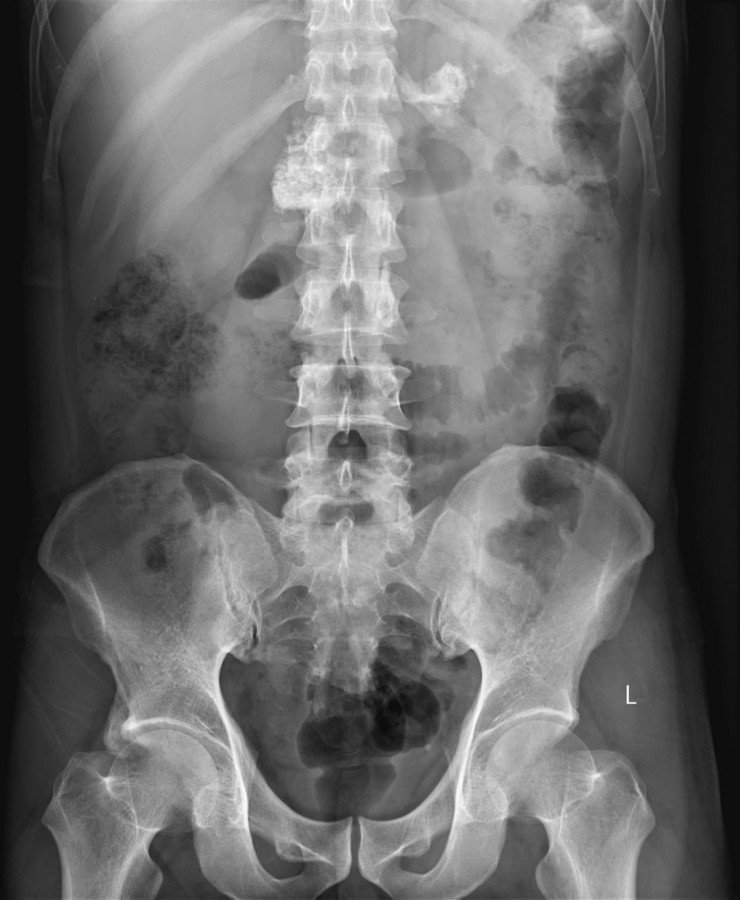

Abdomen : Case 6

History :  A 52-year-old male with abdominal pain.

D. Calcified pancreas

Calcified pancreas

Pancreatic calcification is a feature of chronic pancreatitis.

• Chronic pancreatitis : Soft tissue calcification which follows the anatomical position of the pancreas